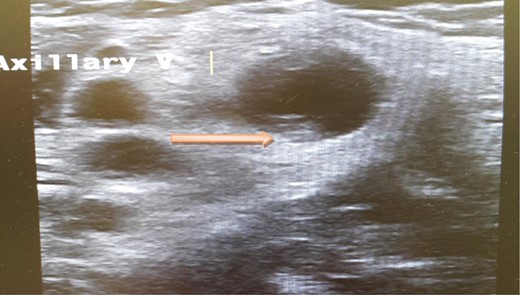

A computed tomography scan of the chest, abdomen and pelvis revealed splenic vein thrombosis (Fig. 1); and a filling defect in the lower lobar segmental branch of the right pulmonary artery consistent with acute segmental pulmonary embolism. A venous duplex scan of the extremities showed thrombosis of the left axillary and basilic veins (Figs 2 and 3). Echocardiogram was normal.

Ultrasound scan of the axillary vein with evidence of thrombus formation.